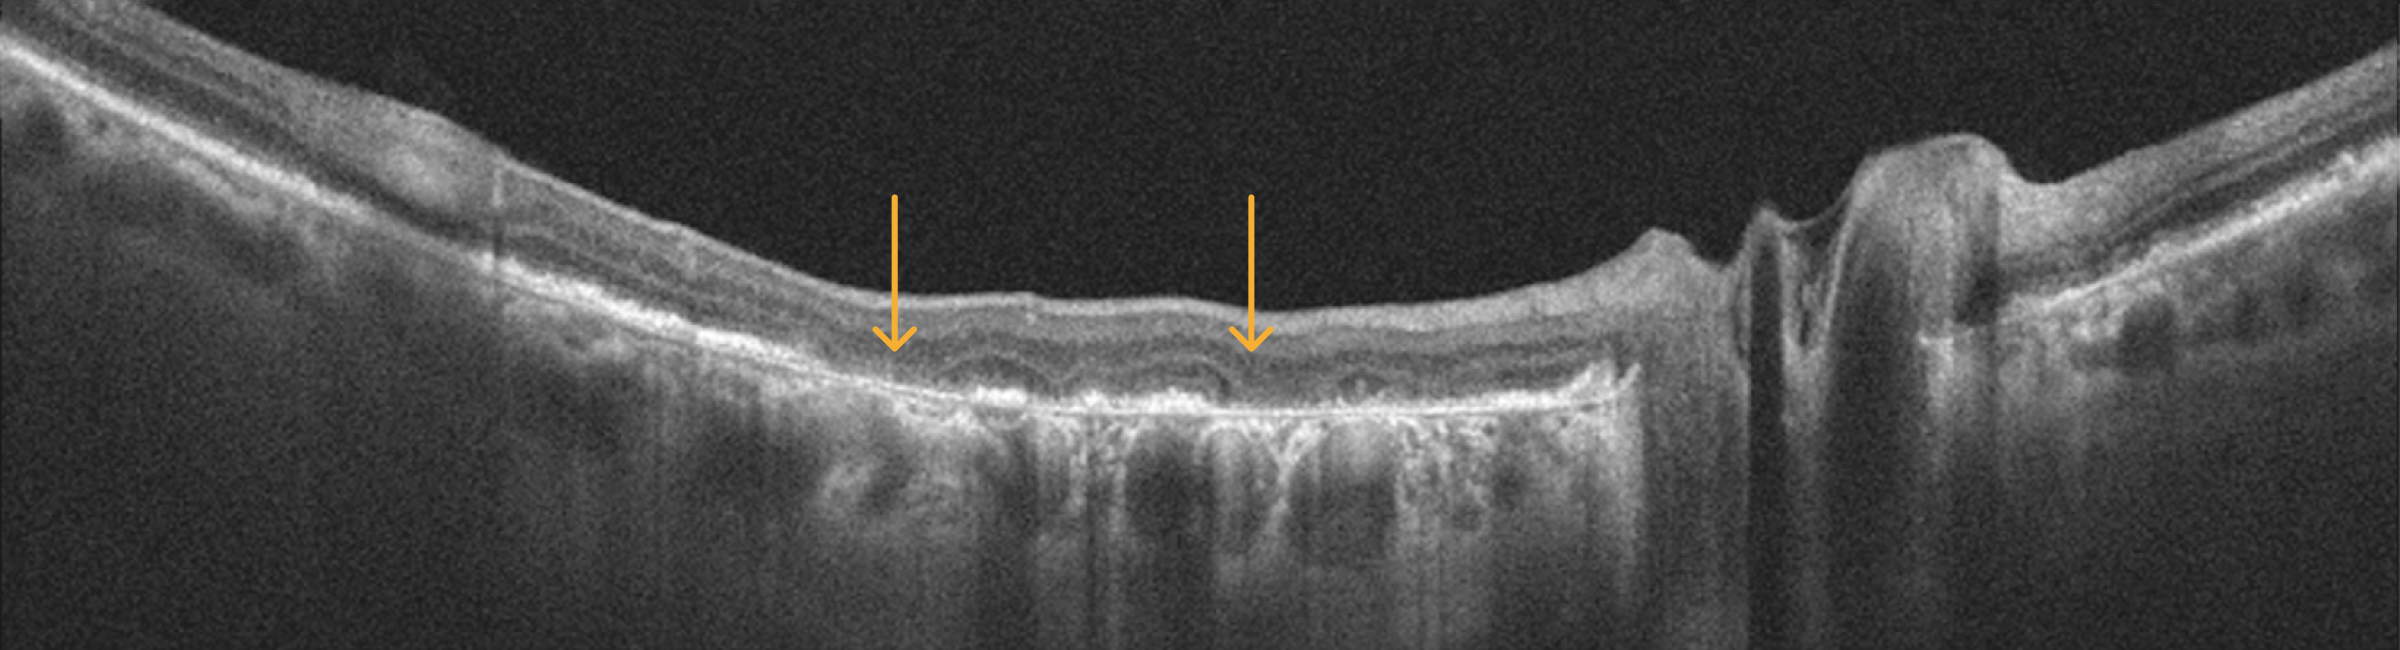

4. Sinking of the INL & OPL

This is sometimes called a "gull-wing" configuration.